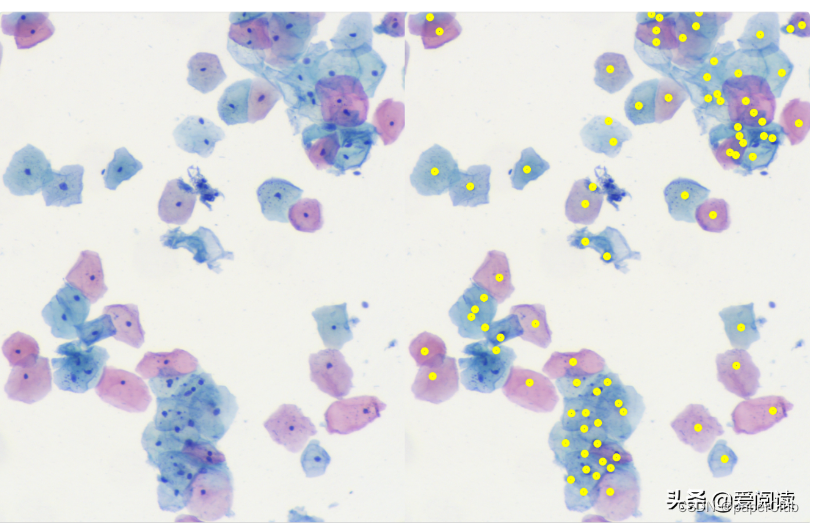

最终细胞核分割定位效果:左边是原图,右边是细胞核行为结果:

例子1:

例子2:

可以看到效果很得不错的。当然这里面还有很大的优化空间。

2.细胞核分割方法2:

左边为原始灰度图像, 右侧为g通道图像,由于图像本身的特征,我们选择g通道进行处理。